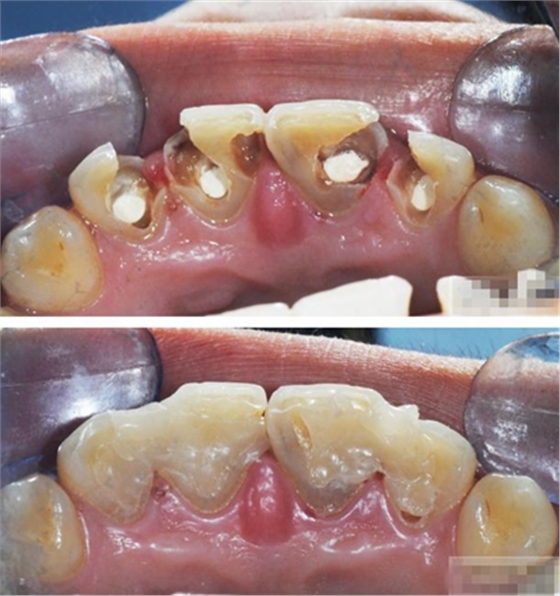

【主訴】上前牙充填物脫落兩個(gè)月

【病史】上前牙一年前行根管治療,充填物部分脫落,自覺影響美觀,從不敢笑,要求先行樹脂修復(fù)。(年齡:14歲)

【檢查】12,11,21,22,均行玻璃離子充填,各牙不同程度部分充填物脫落,探(—),叩(—),冷刺激無反應(yīng),無松動(dòng),牙齦顏色粉紅,質(zhì)地堅(jiān)實(shí)而有彈性,點(diǎn)彩正常,牙結(jié)石(—);牙髓活力測試無反應(yīng)。

【診斷】12,11,21,22牙體缺損